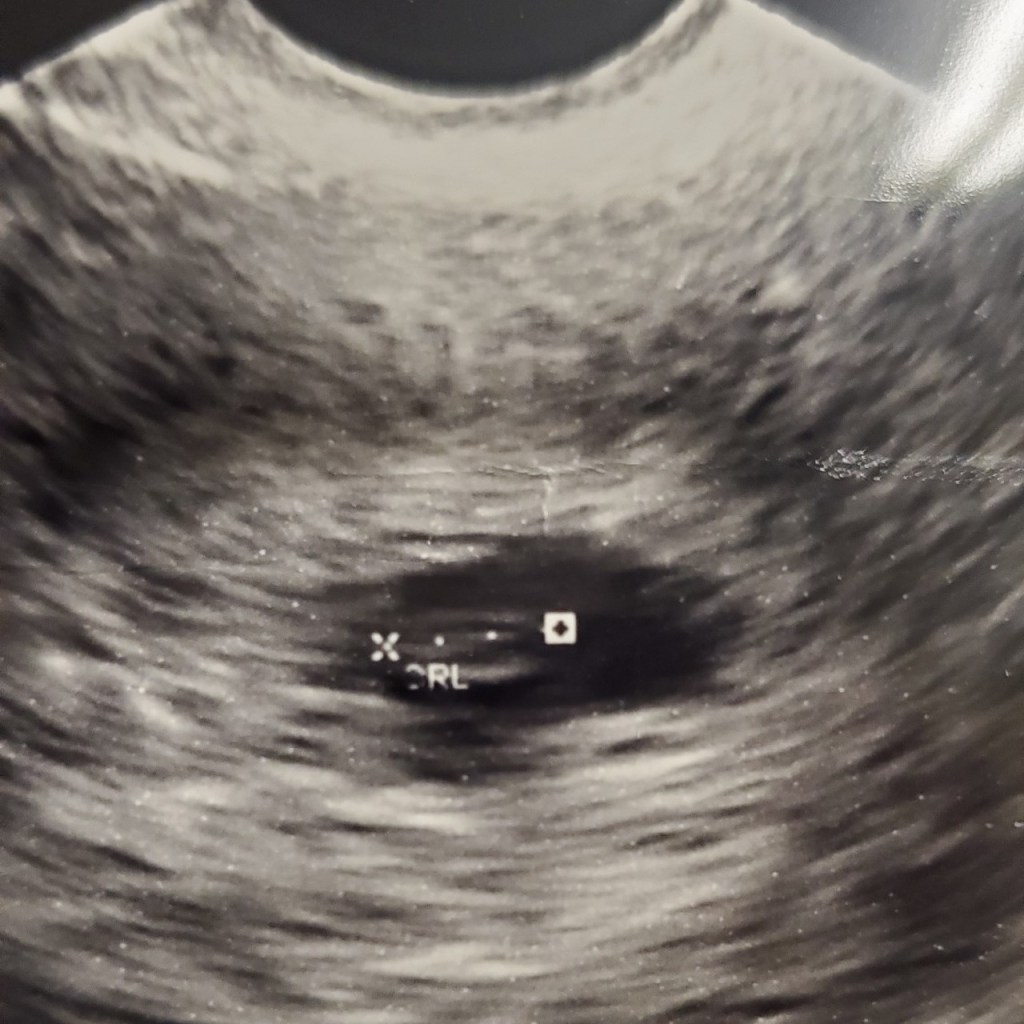

I called my husband and told him I booked a last minute appointment that afternoon. At the ultrasound office we waited nervously as the sonographer started up the ultrasound machine and began the scan. Before the sonographer could tell me what was going on, I already knew for myself. Being a doctor I knew what to look for. I saw no flickering of a heart beating…. I heard no heartbeat… I saw no movement….

The sonographer looked at us quietly and said she will use another ultrasound machine. She switched the ultrasound machine and repeated the scan. Once again we saw no flickering of a heart beating…. we heard no heartbeat… we saw no movement…. My baby’s heart had stopped beating. I immediately broke down in tears. She sent me to the hospital for confirmation and of course the repeat ultrasound there showed the same thing. HOW? How can this happen to me TWICE in just 5 months. HOW?! I felt broken…..